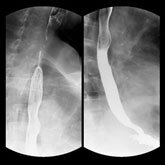

当院は循環器専門病院である一方、予防医学センターでは上部消化管造影検査も行っており、食道や胃に対してバリウムを用いた検査により、病気の早期発見が可能となっております。